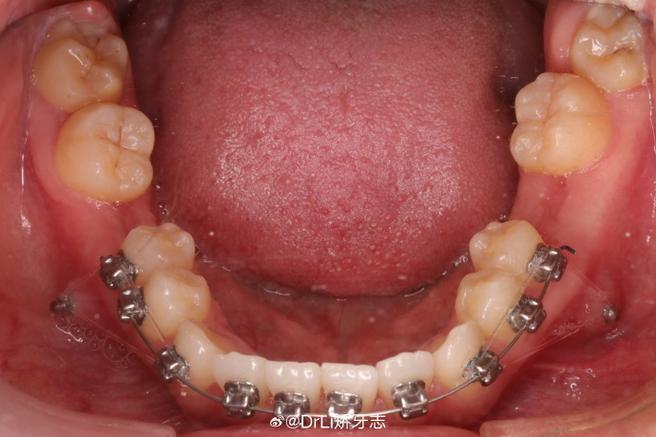

- 口腔卫生维护不当:正畸期间,口腔内托槽、弓丝等装置易堆积食物残渣和菌斑,若清洁不到位,支抗钉周围会成为细菌滋生的“温床”,形成菌斑生物膜,导致局部感染性炎症。

- 加强口腔清洁:使用软毛牙刷轻柔刷牙,重点清洁支抗钉周围,可配合正畸专用小头牙刷或冲牙器,避免用力过猛;每日用生理盐水(或温开水)含漱3-4次,每次30秒,减少菌斑堆积。

- 强化口腔卫生维护:正畸期间使用牙线、冲牙器每日清洁牙缝,配合含氟牙膏预防龋齿;每3-4个月进行一次专业洁治,清除牙结石和菌斑。